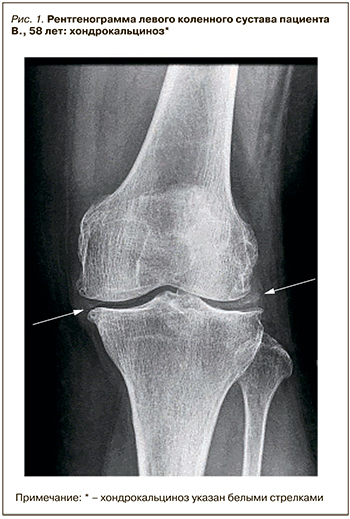

В ноябре 2018 г. без видимых причин (нарушение диеты, употребление алкоголя, дегидратацию пациент отрицает) на фоне сохраняющегося нормального уровня мочевой кислоты пациент отметил последовательное развитие артритов коленных суставов, затем левого плечевого сустава и суставов кистей. В связи с этим в декабре 2018 г. больной обратился на прием в Медицинский научно-образовательный центр МГУ им. М.В. Ломоносова. При осмотре выявлены артриты проксимальных межфаланговых суставов обеих кистей, обоих коленных суставов, плечевого сустава слева. При обследовании уровень мочевой кислоты составил 320 мкмоль/л, СРБ – 20 мг/л, СОЭ – 26 мм/ч. Число болезненных суставов – 8, припухших суставов – 6. С целью исключения дебюта ревматоидного артрита проведено иммунологическое исследование: уровни ревматоидного фактора (РФ) и антител к циклическому цитруллинированному пептиду оказались в норме. Также был проведена дифференциальная диагностика с ПАП: рентгенография коленных суставов выявила типичный признак ПАП – хондрокальциноз (рис. 1).

Трудность приведенного клинического случая при верификации диагноза заключалась как в схожести клинических проявлений ПАП и ранее установленной подагры (данных в пользу обострения которой получено не было), так и в симулировании ПАП клиники ревматоидного артрита (стойкие симметричные артриты обеих кистей, повышение сывороточного уровня СРБ), который в соответствии с диагностическими критериями АСR/EULAR 2015 г. подтвержден не был [5]. С учетом стойкой нормоурикемии, отсутствия данных в пользу ревматоидного артрита было предположено наличие у пациента еще одного заболевания, вызвавшего обострение. Согласно рекомендациям ACR/EULAR, решающее значение в диагностике микрокристаллических заболеваний имеет артроцентез с исследованием синовиальной жидкости для выявления кристаллов [1, 2, 6]. В результате обследования по данным цитологического исследования синовиальной жидкости были выявлены соли пирофосфата кальция, по данным рентгенографии коленных суставов – типичные признаки хондрокальциноза; это позволило установить диагноз «пирофосфатная артропатия. Подагра, хроническое течение. Подагрический артрит вне обострения».